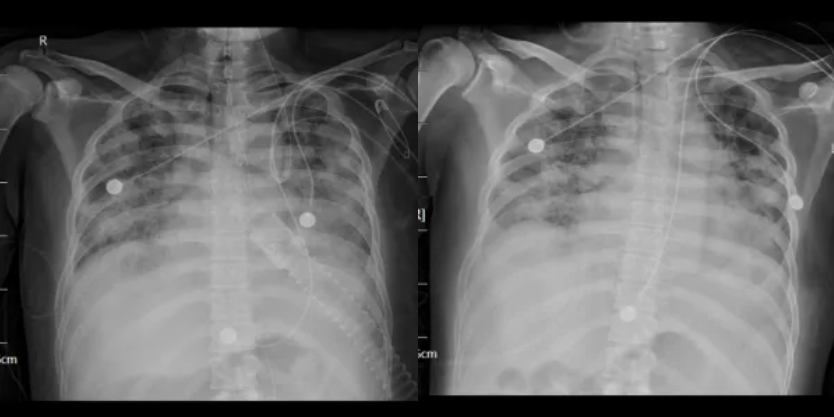

经过治疗后患者病情逐渐好转,呼吸机需氧浓度及PEEP逐渐下调,复查血气氧和指数逐渐好转,9月17日复查胸部CT(见图4),氧合指数165,予拔除气管插管,改日间高流量(流速 40L/min,氧浓度60%)与夜间无创呼吸机辅助通气(IPAP12cmH2O EPAP 5cmH2O FiO2 45%)交替,复查血气氧和指数P/F 182。予逐渐下调氧浓度复查氧和指数进一步升高(见图5),监测患者外周血感染指标超敏C反应蛋白降至基本正常(见图6)。调整鼻导管吸氧,10月7日复查胸部CT双肺慢性及间质改变较前明显吸收(见图7)。监测患者外周血KL-6水平较前明显下降(见图8)。

图5:患者拔管后复查床旁X线(左:2025年9月22日 高流量与无创交替 FIO2 70% P/F 195;右:2025年9月29日 5L/min鼻导管吸氧 P/F 292)